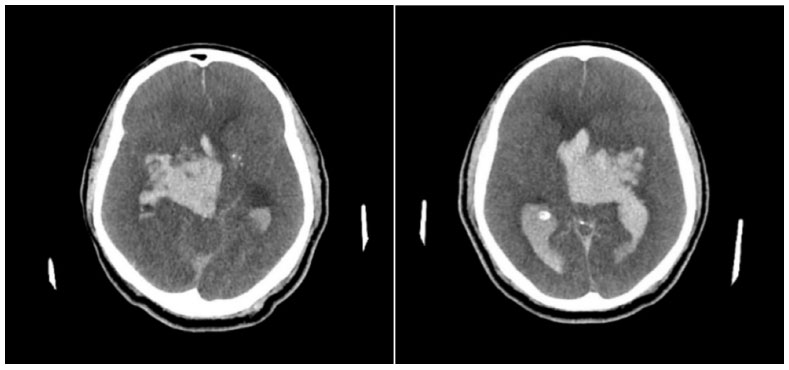

Paciente do sexo masculino, 62 anos, diabético e hipertenso, deu entrada no Departamento de Emergência com queixa de cefaleia súbita e rebaixamento do sensório, 3 horas antes de sua chegada. Seus sinais vitais da entrada mostravam hipertensão com PA 163x110 mmHg, taquicardia com FC 110 bpm, com boa saturação em ar ambiente de 97%, apesar do quadro de rebaixamento e escala de coma de Glasgow de 10 (AO 3 RV 3 RM 4). Poucos minutos após sua chegada, antes mesmo que fosse levado para realizar neuroimagem, paciente apresentou episódio de convulsão tônico-clônica generalizada, ocasião na qual houve piora do rebaixamento. Foi hidantalizado e intubado na sequência. Apesar das medidas para neutroproteção, paciente apresentou instabilidade hemodinâmica, com hipotensão de 92x57 mmHg. Não havendo condições de transporte para realizar neuroimagem, foi realizado ultrassom beira leito da bainha do nervo óptico, que mostrou aumento desta com achado de 8,42 mm de dilatação, corroborando com a hipótese de hipertensão intracraniana que ditava o quadro clínico. Foram iniciadas medidas para aumento da pressão intracraniana, assim como correção da hipotensão, com posterior estabilização hemodinâmica. Realizou, então, neuroimagem, com achado de volumosa hemorragia intraparenquimatosa centrada em núcleos da base à direita, associada a hemoventrículo difuso e sinais de hipertensão intracraniana (Figuras 1 e 2). Foi optado por neurocirurgia manter conduta conservadora do quadro.